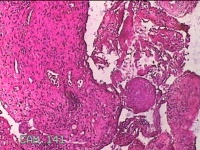

子宫左侧壁残留妊娠物

性别

女

年龄

40岁

临床诊断

稽留流产 药流失败 宫腔粘连

一般病史

停经5月余,要求终止妊娠。

标本名称

大体所见

灰白暗红色不规则碎组织1.5x1.3x0.3cm一堆,内有少许绒毛样组织。

见胎盘绒毛。

凝血中见退 变蜕膜和机化绒毛。